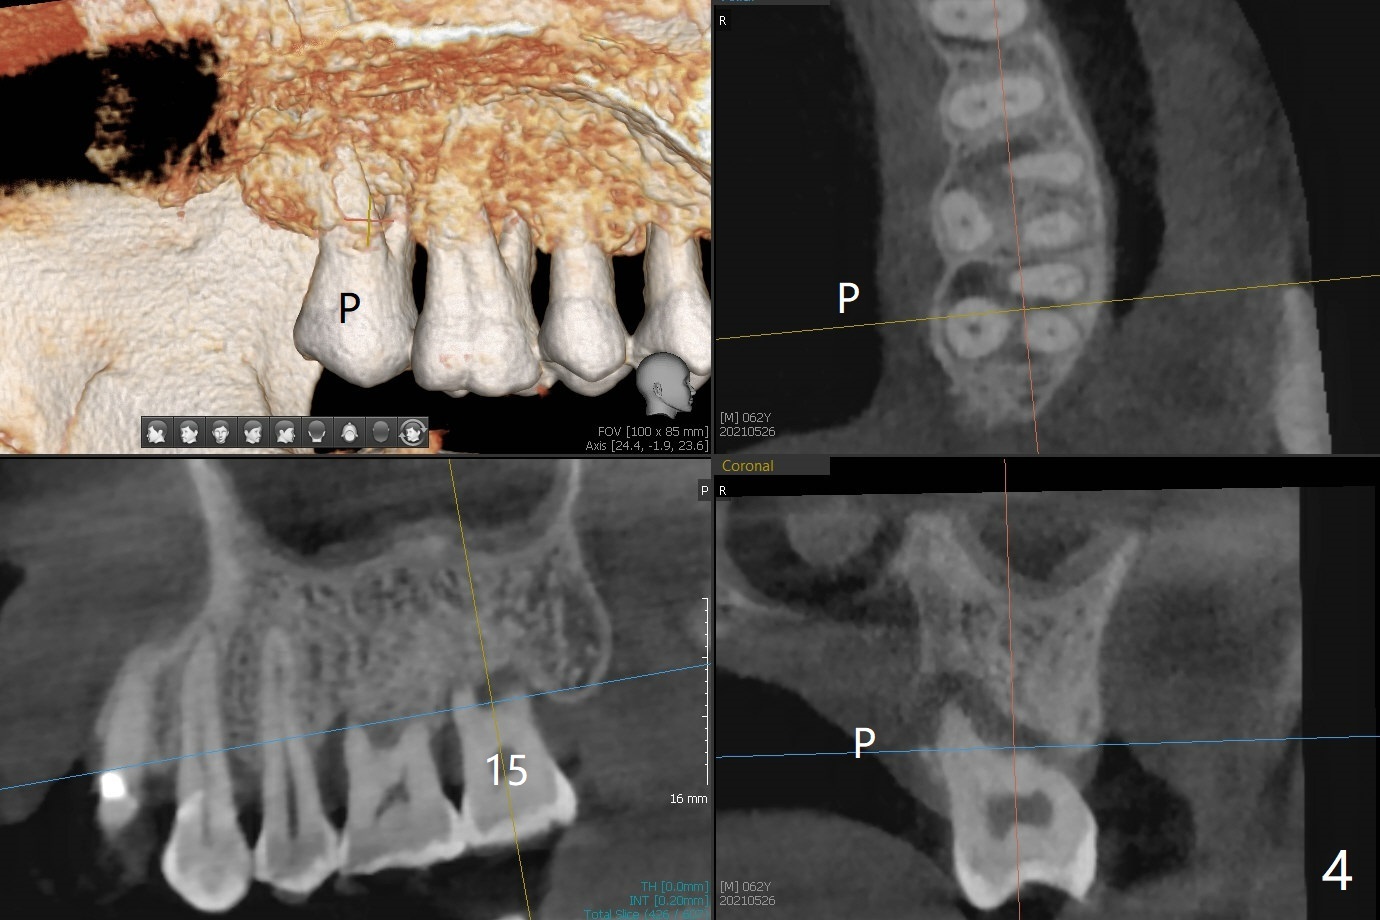

A 62-year-old man with sign of bruxism (#19 porcelain chip (Fig.2), 28 fracture/extraction) complains of severe mastication pain at #15 (Fig.1). More severe pain is elicited when the buccal cusps bite on a bite stick than the palatal one (Fig.3 with suspicious crazing lines). CT shows bone loss around the palatal root (Fig.4 P). A 5x11.5 mm implant will be placed immediately (Fig.5). The bone at #28 is able to hold a 3.5x13 mm implant (Fig.6). It is extremely difficult to take photos for 2nd molar crack line with a regular camera (Fig.3). The Shining Oral Scanner acts additionally as an intraoral camera. As a busy clinician, I do not have time to take photos for #19 porcelain chip. My assistants take over the task. After work, I am able to have bumper harvest. With the information just mentioned, I will be in a better position to present a more comprehensive treatment plan to the patient when treatment at #15 is finished: remove #18-20 bridge, place an implant at #19 and fabricate new crowns at #18 and 20.